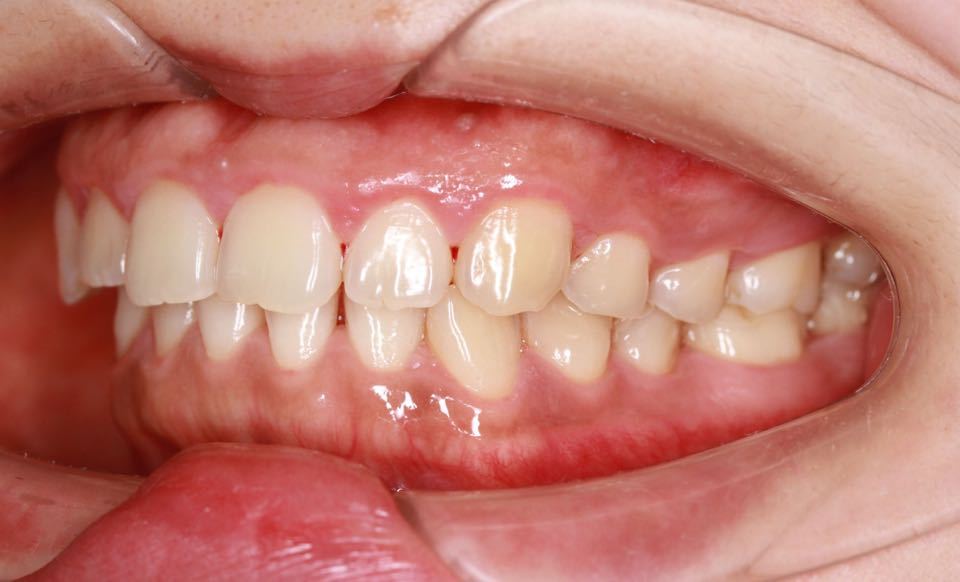

矫正后口内照:

治疗改善:关闭散隙,调整中线。

目前阶段:全口牙齿排列整齐,中线居中。前牙覆合覆盖正常,尖磨牙关系达I类咬合关系。总疗程约18个月。